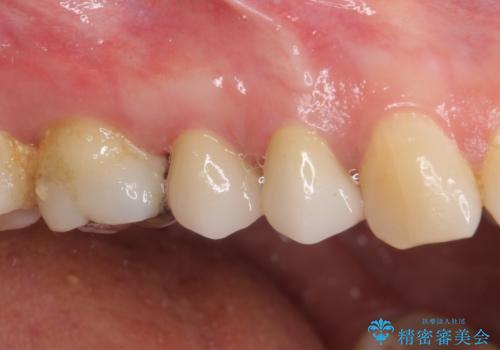

透明感のある自然な仕上がりとなり、患者様には大変満足していただきました。